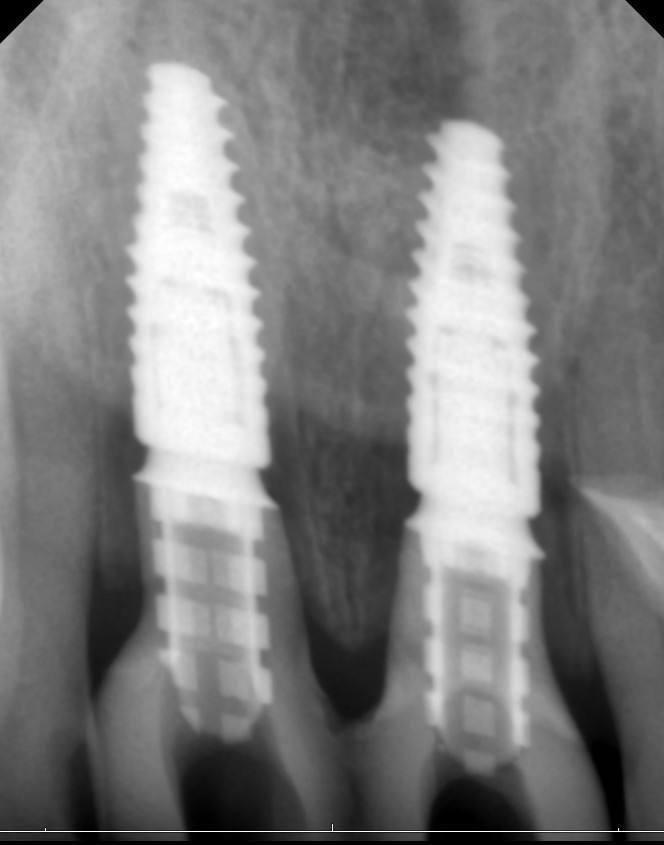

Очень важно во фронтальном отделе корректное параллельное расположение имплантатов во всех трех плоскостях.

Фото 6, 7.